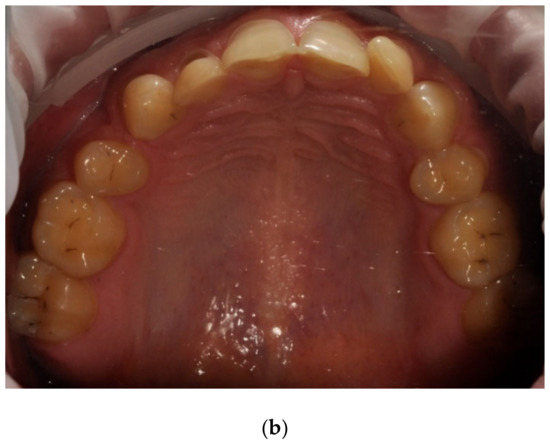

Figure 7. (a,b) Man, 33 y.o. Advanced internal and external erosion. The patient reported regular vomiting and consumption of approximately 6 L of Coca-Cola per day over a period of more than 6 months—front teeth and upper arch.

Ijerph 20 04792 g007aIjerph 20 04792 g007b

Examples of erosive defects occurring in the examined patients are presented in Figure 6, Figure 7a,b and Figure 8a–c.